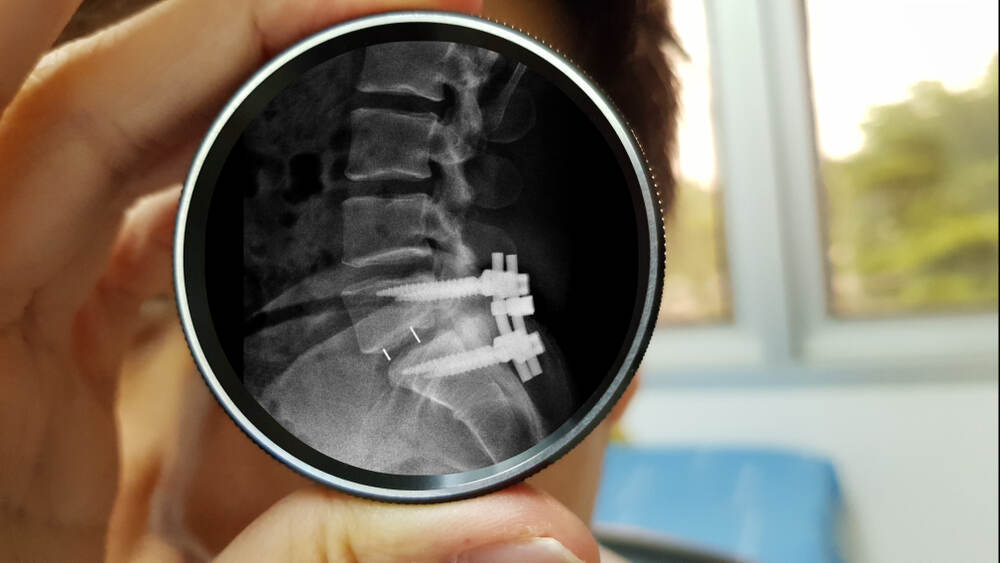

Spinal fusion surgeries play a crucial role in the treatment of various spinal conditions, providing much-needed stability and relief to patients. Two commonly performed procedures, XLIF (eXtreme Lateral Interbody Fusion) and TLIF (Transforaminal Lumbar Interbody Fusion), have gained prominence in the field of spinal surgery. If you're considering or researching these procedures, understanding their differences is vital to make an informed decision about your treatment options.

TLIF is commonly indicated for conditions such as degenerative disc disease, spondylolisthesis, and spinal instability. By removing the source of compression and instability, TLIF helps restore proper alignment, decompress nerves, and promote spinal stability. This is achieved by placing an interbody cage, typically made of a bone graft or a synthetic material, between the adjacent vertebrae, facilitating fusion and enhancing stability.